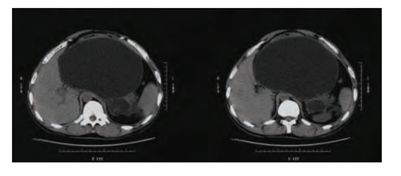

波科支架怎么样五分钟解决胰腺假性囊肿,波科AXIOS支架和电灼增强输送系统 | 盖伦奖提名医械详解Ⅹ_https://www.jmylbn.com_新闻资讯_第5张

腹部CT提示胰腺巨大假性囊肿压迫胃部